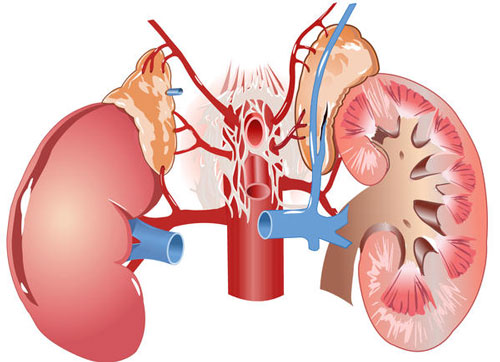

نشانه های رایج بیماری های کلیوی

۹۰ درصد افرادی که دارای نشانههای بیماری های کلیوی هستند، از این موضوع مطلع نیستند. با ما همراه باشید تا با نشانههای رایج بیماری های کلیوی آشنا شوید.

ده نشانه بیماری های کلیوی

از جمله عواملی که باعث بروز بیماریهای کلیوی میشوند، میتوان به فشارخون بالا، دیابت، سابقه خانوادگی بیماری کلیوی و سن بالای ۶۰ سال اشاره کرد.

اگرچه تنها راه برای اطمینان از وجود بیماریهای کلیوی، انجام آزمایش است؛ اما این بیماریها یک سری نشانه فیزیکی نیز دارند. گاهی اوقات افراد این نشانهها را به بیماریهای دیگری نسبت میدهند؛ زیرا در افرادی که دچار بیماریهای کلیوی هستند، تا زمانی که بیماری به مراحل شدید برسد، نشانهها بروز نمیکنند.

در ادامه به ۱۰ نشانه رایج اشاره میکنیم که نشان میدهند دچار بیماریهای کلیوی هستید.

۳- پوستتان خشک بوده و به شدت میخارد. کلیههای سالم، کارهای مهم زیادی انجام میدهند. این اندام داخلی بدن مایعات اضافی و باقیمانده را از بدن خارج میکند، به تولید سلولهای قرمز خون کمک میکند، استخوانها را قوی نگه میدارد و برای حفظ میزان مناسبی از مواد معدنی در خون تلاش میکند. پوست خشکی که میخارد، میتواند نشانهای از کمبود مواد معدنی و بیماری استخوانی باشد که معمولاً با بیماریهای کلیوی پیشرفته همراه هستند. زمانی که کلیهها نتوانند تعادل مواد معدنی و مغذی را در خون حفظ کنند، این مشکلات بروز میکند.